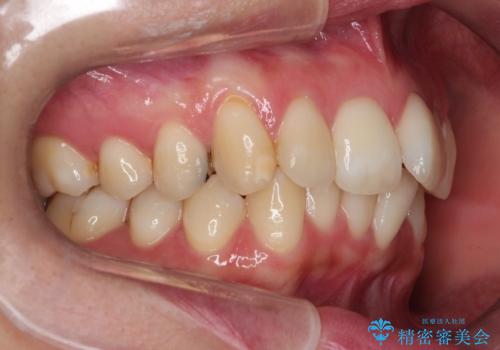

奥歯の噛み合わせは綺麗に噛んでいたため、前歯の叢生(でこぼこ)を、短期間で治療完了するように計画しました。

奥歯の噛み合わせは整っていたため、前歯の並びを美しく修正することに専念できました。マウスピース矯正による治療で短期間で改善しました。